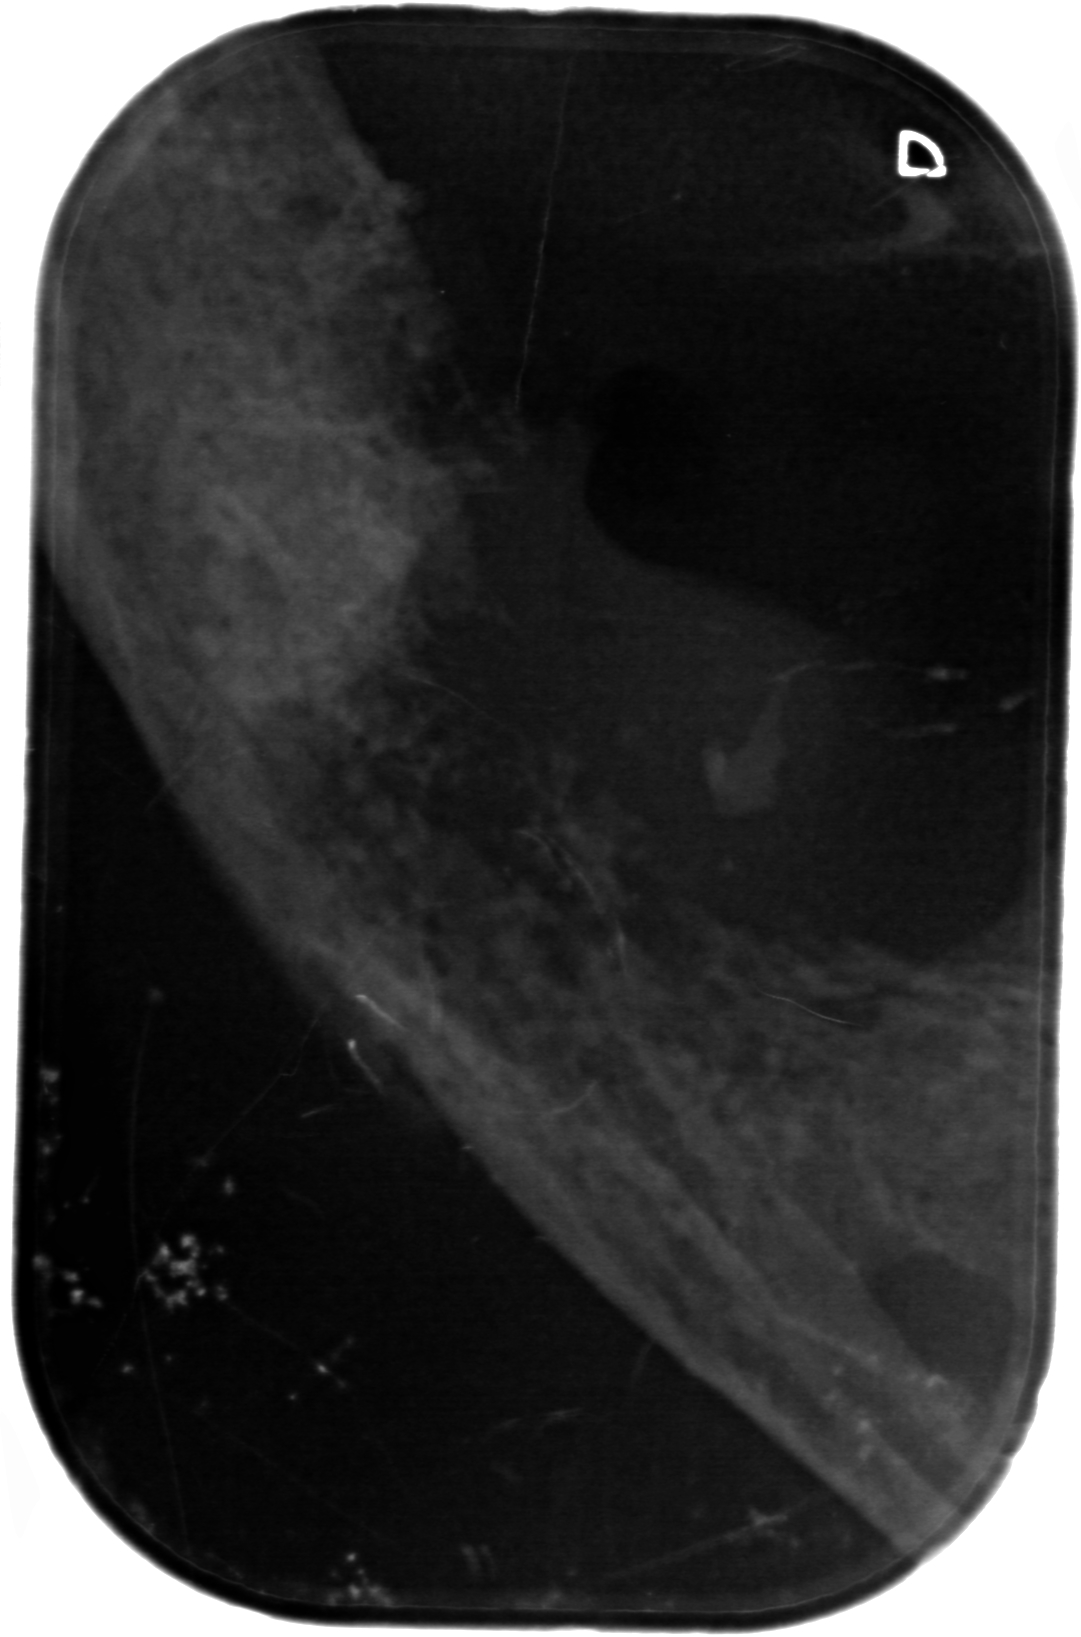

Kæbekræft hos Shana-Mio, 3, 24. januar 2013

Fuld størrelse er

1081 × 1637

pixel

Kæbekræft hos Shana-Mio, 2, 24. januar 2013

Kæbekræft hos Shana-Mio, 4, 24. januar 2013